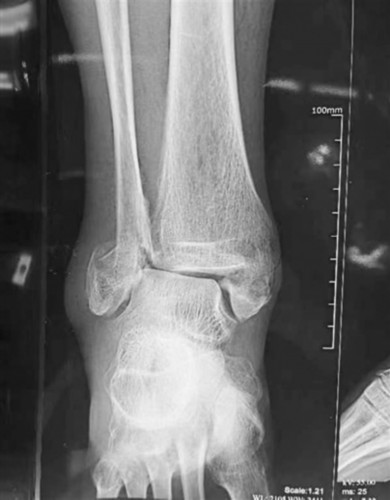

今年68岁的张先生,在一周前雨后遛狗时滑倒,右脚不能动了,经过沈阳医学院附属中心医院诊断为“右三踝粉碎性骨折”,需要手术治疗。张先生患“糖尿病”20年未系统治疗,他和家属对手术有很多顾虑,“年龄大了、血糖高、受罪”,想保守治疗。

记者了解到,68岁的张先生被医院诊断为“右三踝粉碎性骨折”(踝关节的内外后三个部分都骨折了,属于比较严重的踝关节骨折)需要手术治疗,他和家人很忐忑。

崔军了解到老人的详细病情后,发现老人的情况符合“手术指征”,患者如果不做手术,走路能力严重受限或者不能走了,会进一步影响心肺功能,还有可能影响到自然寿命。

崔军认为,糖尿病是影响手术愈后或者感染的一个重要的因素,现在糖尿病人也特别多,但是糖尿病不是绝对的手术禁忌症,它是相对的,把血糖调整好了之后就可以手术。老人入院后控制血糖并且完善相关检查评估,“手术指征”明确,可以手术治疗。